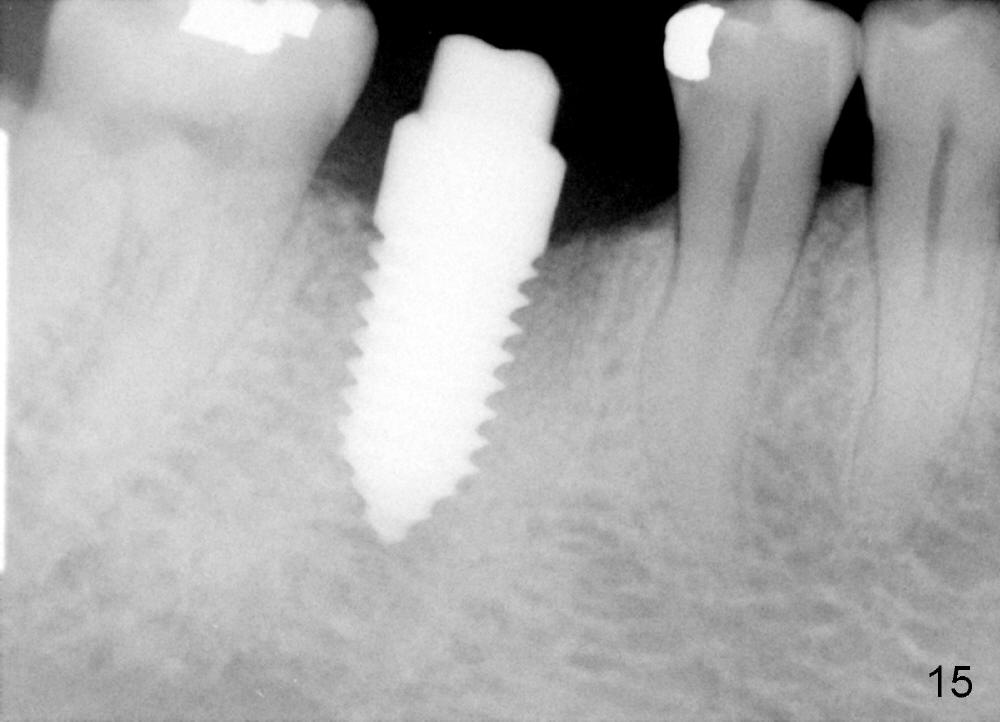

A 38-year-old lady agrees to have implant placement 7 years after loss of the crown of the lower right first molar (Fig.1,2). When the tooth is extracted, the septum is found to be low (Fig.3,4). To confirm it, a PA is taken (Fig.5). To initiate an osteotomy in the septum, it is trans-sectioned with thin osteotomes as shown in Fig.4 insert (black line). A 2 mm pilot drill is placed in the septum (Fig.6: P). The osteotomy is enlarged by 2.5-4.0 mm reamers (Fig.7,8), followed by insertion of 6x17 mm tapered tap at the depth 14 mm (Fig.9). The osteotomy is further enlarged by 4.5 and 5.0 mm reamers. A 6.0x14 mm one piece implant is placed initially. The trajectory is not ideal. A 6.0x14 mm one piece implant is placed initially. The trajectory is not ideal. The implant is removed from the osteotomy partially and reinserted with improved trajectory (Fig.11, compare to Fig.10 (red line)). Primary stability is high. There is not much bone mesiodistally so that the trajectory is easily changed in that direction. After abutment preparation, mixture of autogenous bone (harvested from reamers) and allograft is placed in the residual mesial and distal sockets (Fig.12). To contain the bone graft, an immediate provisional is placed (Fig.13 P). The occlusal plane of the provisional is significantly lower than that of the adjacent teeth to avoid micromovement of the implant. The patient is advised to eat soft food on the left side. Six days postop, the patient returns for prophy. The provisional is removed; the bone graft appears to be incorporating into the socket (Fig.14). After recementation, the provisional remains in place for 3.5 months; PA shows increased bone density in the mesial and distal sockets (Fig.15, compare to Fig.5,11). Due to insurance coverage, the patient defers fabrication of definitive restoration for at least 7 months. The immediate provisional is finally lost 8.5 months postop: the gingiva attaches to the 1-piece implant (Fig.16), while the density of the mesial socket increases (Fig.17 *) with formation of the cortex (lamina dura) coronally (v). Before the provisional (Fig.18 P) is removed for cementation of the definitive restoration, black shadow (*) is noted over the buccal gingiva. It is partially due to buccal placement (Fig.19) and partially due to buccal atrophy over a period of 10.5 months postop. How to prevent buccal placement? Positioning the first pilot drill in the septum buccolingually is a key. Eleven months post crown (Fig.20 C) cementation, the black shadow remains, but there is no tenderness. If the implant threads are immediately underneath the periosteum, there is tenderness.